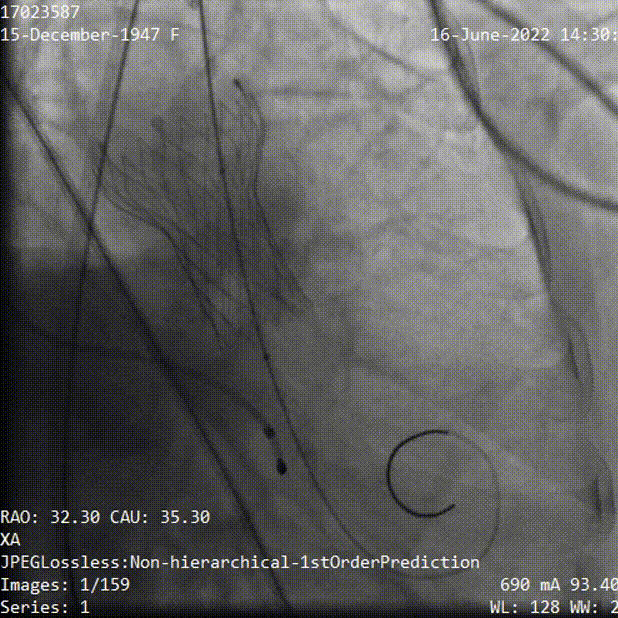

手术过程

主动脉根部造影,主动脉瓣开放受限,中度反流,采用20mm球囊预扩,有明显腰征,无造影剂渗漏,测压差70mmHg左右。

主动脉根部造影

球囊预扩

TaurusElite输送系统轻松过弓、跨瓣,AV23瓣膜瓣环上0mm定位释放,到工作位后造影显示瓣膜形态、位置良好。

瓣膜定位

释放到工作位观察

释放脱钩后瓣膜形态、位置良好,冠脉血流灌注正常,微量瓣周漏;采用22mm球囊后扩,无压差,无瓣周漏;弓部血管造影未见异常。

球囊后扩

术后根部造影

术后压差

术后经胸超声